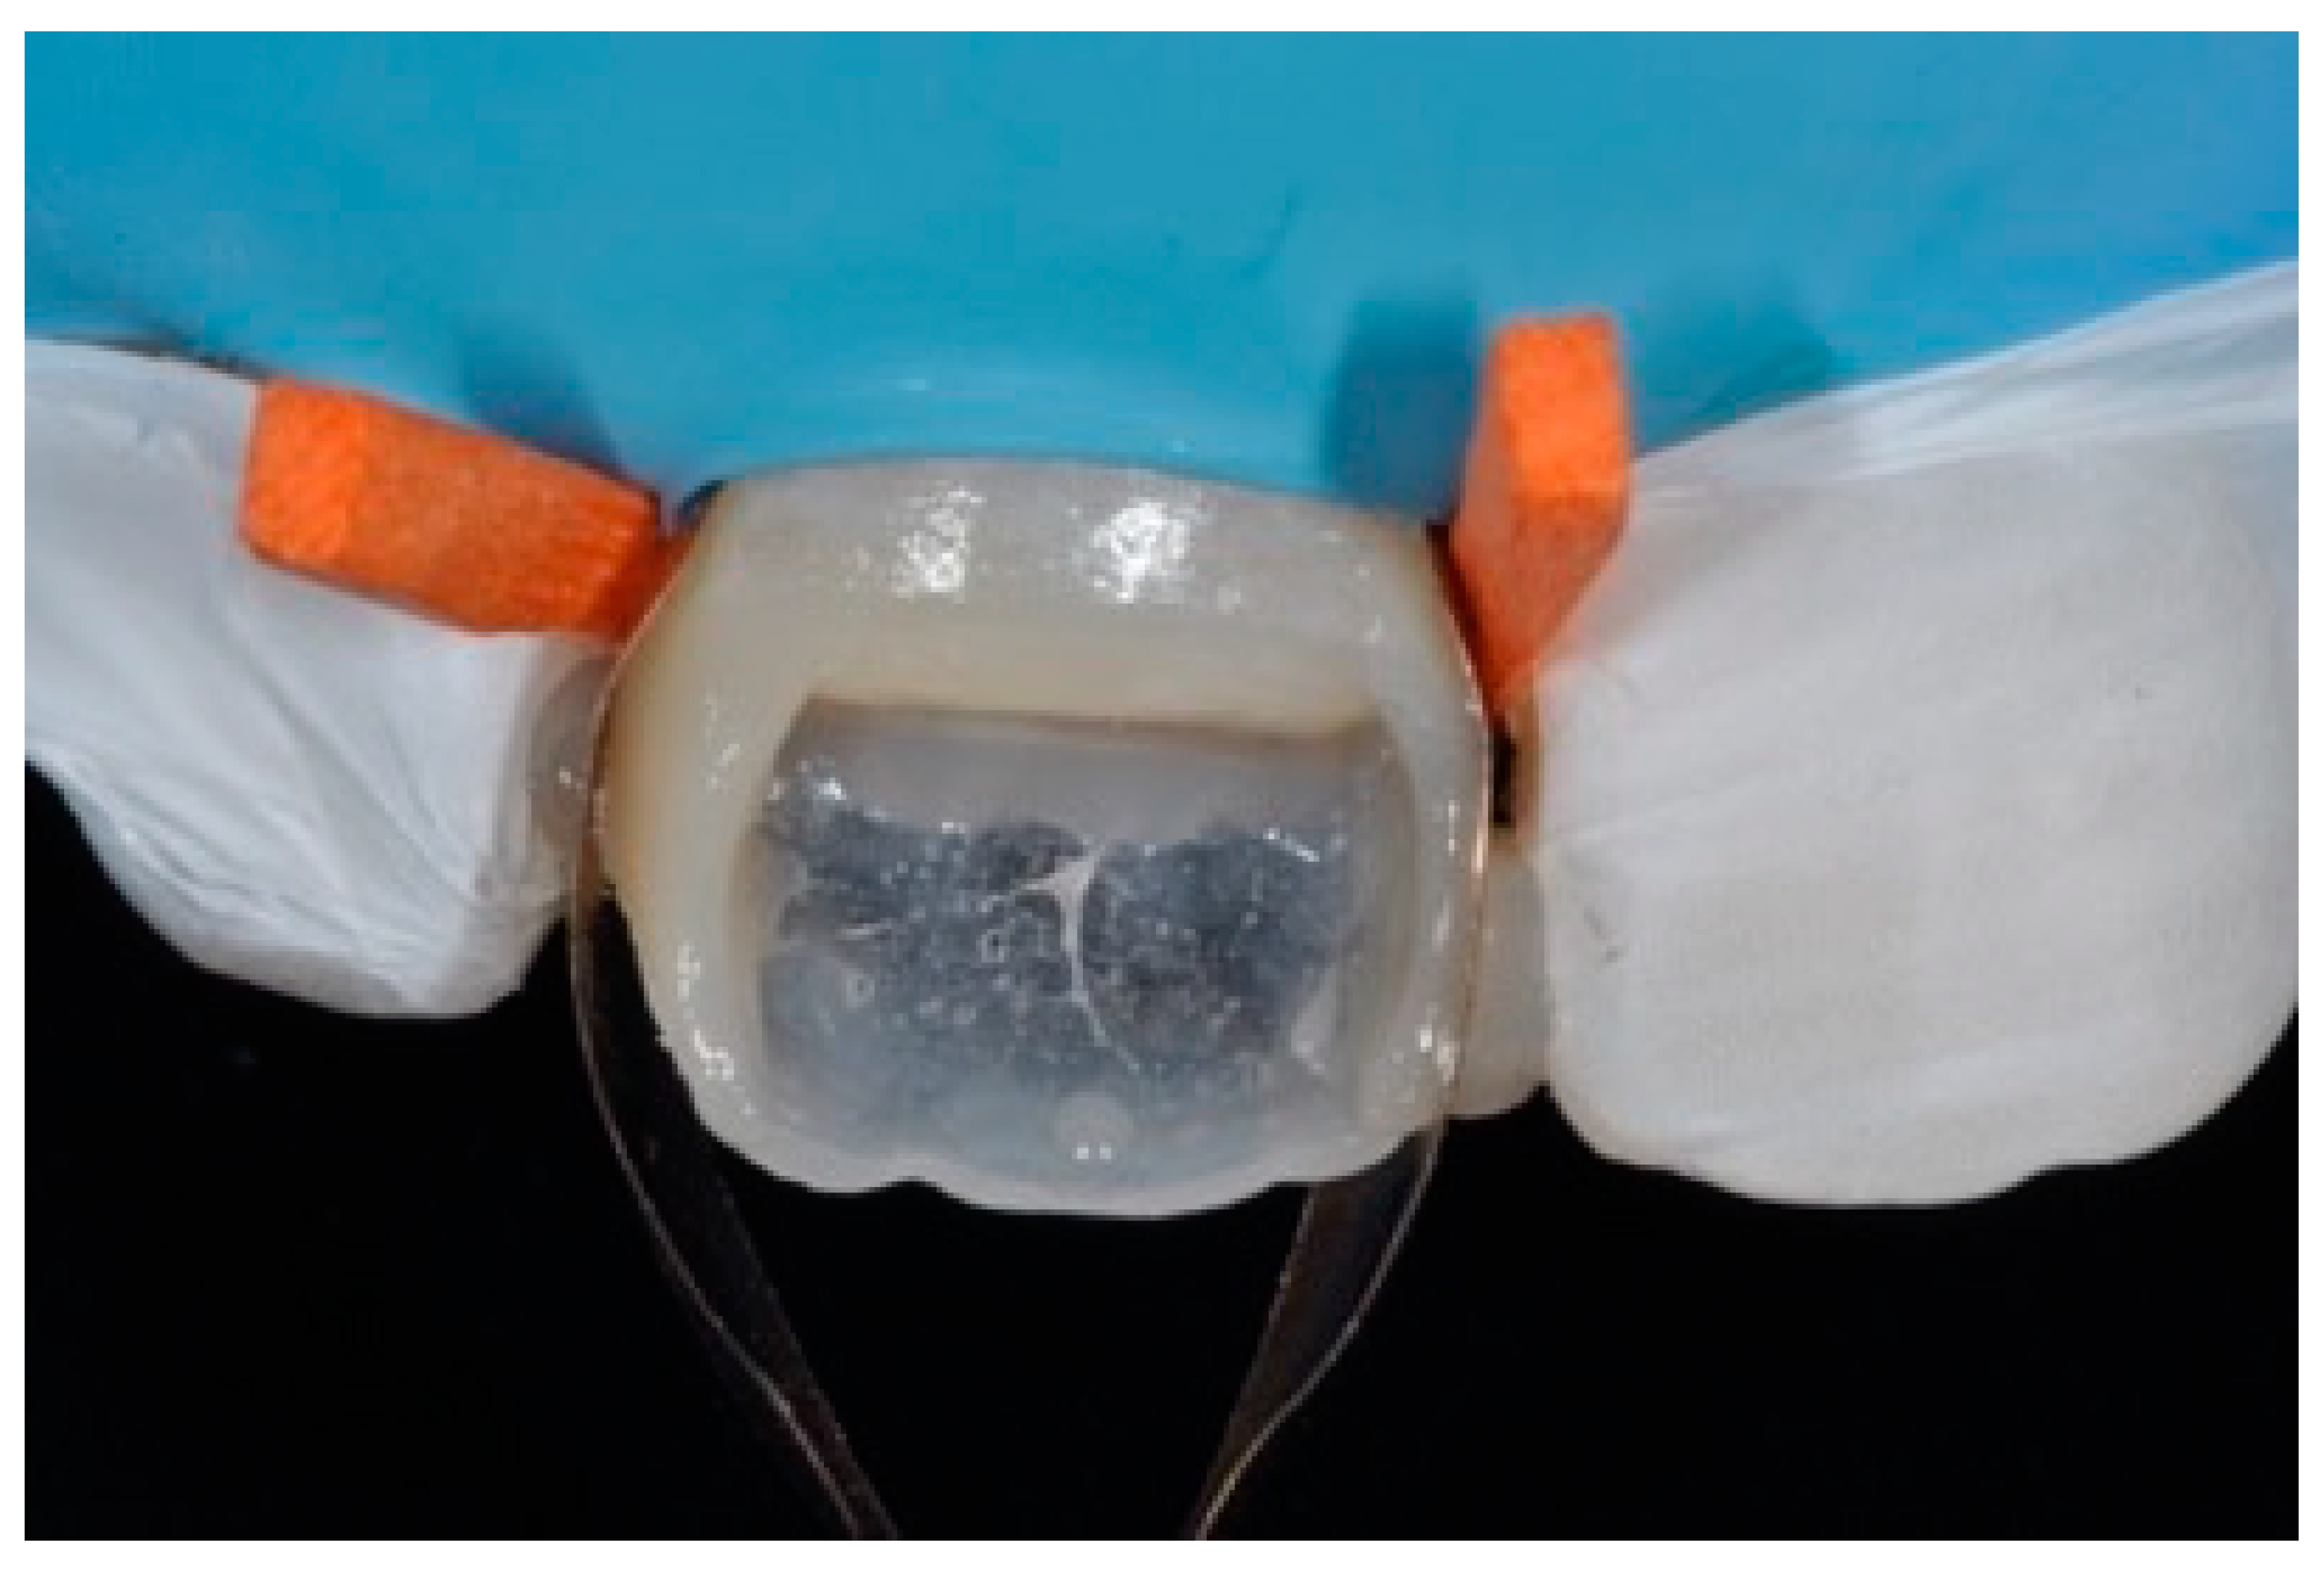

A 53-years old man presented to the dental office asking for the restoration of the mesial incisal angles of both central incisors (Figure 40). After preliminary shade analysis (using the button-try technique [14]) an attentive management of opaque and translucent shades was required to esthetically solve this case. After isolation with rubber dam, preparation, and adhesive procedures (Optibond FL, Kerr, Bioggio, Switzerland) the frame was completed using a translucent shade (Mosaic, ET, Ultradent Products, South Jordan, UT, USA) for palatal wall and an opaque material (Mosaic, A2, Ultradent Products, South Jordan, UT, USA) for incisal margin and interproximal walls. The external and internal excesses of the frame were modified (as described in Section 2.1.2) to obtain a uniform thin opaque outline as planned during the preliminary color/opacity analysis. This modification was performed to avoid the unfavorable uncovering of translucent areas during final finishing procedures that could result in an unaesthetic outcome. Once the definition of the external frame was completed, the mesial mamelon was modeled (Mosaic, A2, Ultradent Products, South Jordan, UT, USA) and the translucent material (Mosaic, ET, Ultradent Products, South Jordan, UT, USA) was applied. Finishing and polishing procedures (Jiffy, Ultradent Products, South Jordan, UT, USA) were completed afterwards.